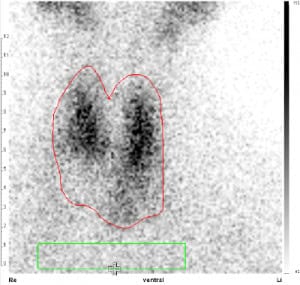

Schilddrüsenszintigraphie

Mit Schilddrüsenszintigraphie wird die Anfertigung eines Funktionsabbilds der Schilddrüse bezeichnet. Hierzu wird schwach radioaktives Technetium-99m in den Arm injiziert und wenige Minuten später mittels einer Gammakamera das von der in die Schilddrüse eingebaute Technetium-99m im Hinblick auf Menge und Verteilungsmuster aufgezeichnet. So lassen sich funktionslose, sog. „kalte“ Knoten von sog. „heißen“ Knoten unterscheiden, also immer gutartigen Befunden mit ungehemmter Schilddrüsenhormonproduktion, die abhängig von ihrer Größe zu einer Überfunktion führen können. Auch können so Schilddrüsenüberfunktionen hinsichtlich ihrer Ursachen und Kröpfe (Strumen) im Hinblick auf ihre Behandelbarkeit mittels Radiojod abgeklärt werden.